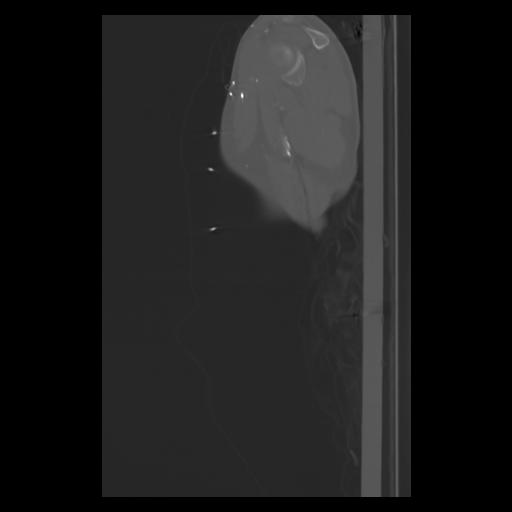

30 CUERPO,CE,Sagittal,3.000,CUERPO,Sagittal,